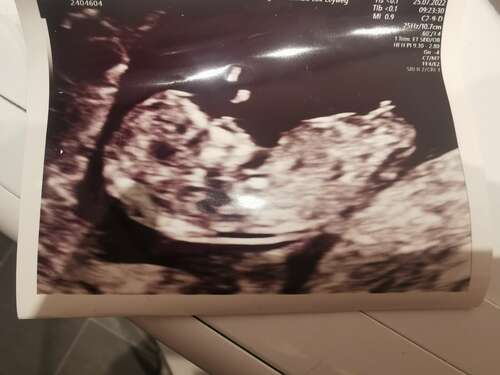

Net mijn 13 weken echo gehad! Wat denken jullie 🥰?

Jongen